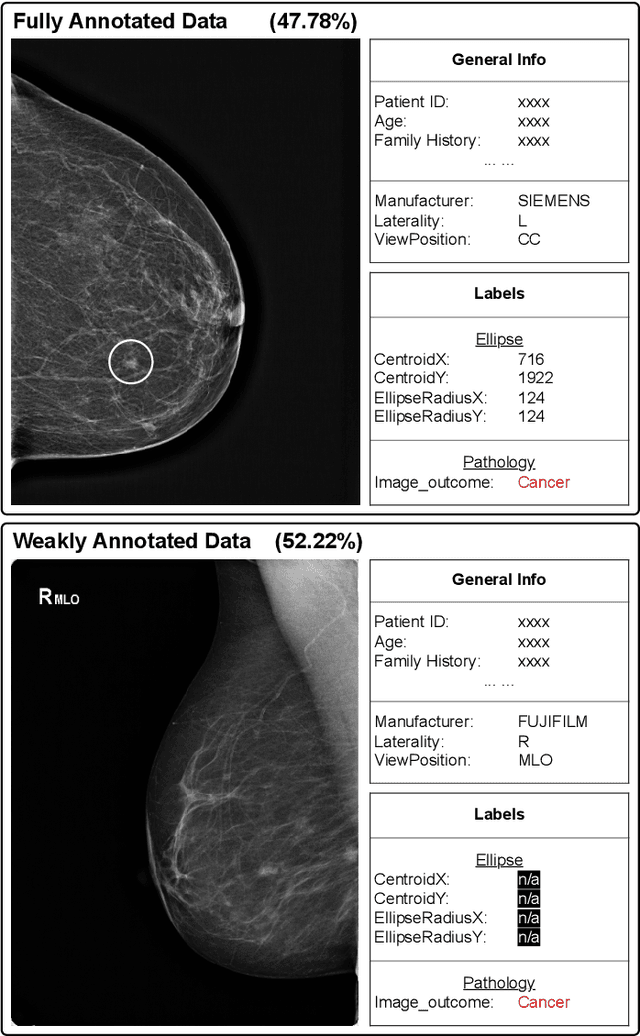

Abstract:Methods to detect malignant lesions from screening mammograms are usually trained with fully annotated datasets, where images are labelled with the localisation and classification of cancerous lesions. However, real-world screening mammogram datasets commonly have a subset that is fully annotated and another subset that is weakly annotated with just the global classification (i.e., without lesion localisation). Given the large size of such datasets, researchers usually face a dilemma with the weakly annotated subset: to not use it or to fully annotate it. The first option will reduce detection accuracy because it does not use the whole dataset, and the second option is too expensive given that the annotation needs to be done by expert radiologists. In this paper, we propose a middle-ground solution for the dilemma, which is to formulate the training as a weakly- and semi-supervised learning problem that we refer to as malignant breast lesion detection with incomplete annotations. To address this problem, our new method comprises two stages, namely: 1) pre-training a multi-view mammogram classifier with weak supervision from the whole dataset, and 2) extending the trained classifier to become a multi-view detector that is trained with semi-supervised student-teacher learning, where the training set contains fully and weakly-annotated mammograms. We provide extensive detection results on two real-world screening mammogram datasets containing incomplete annotations, and show that our proposed approach achieves state-of-the-art results in the detection of malignant breast lesions with incomplete annotations.